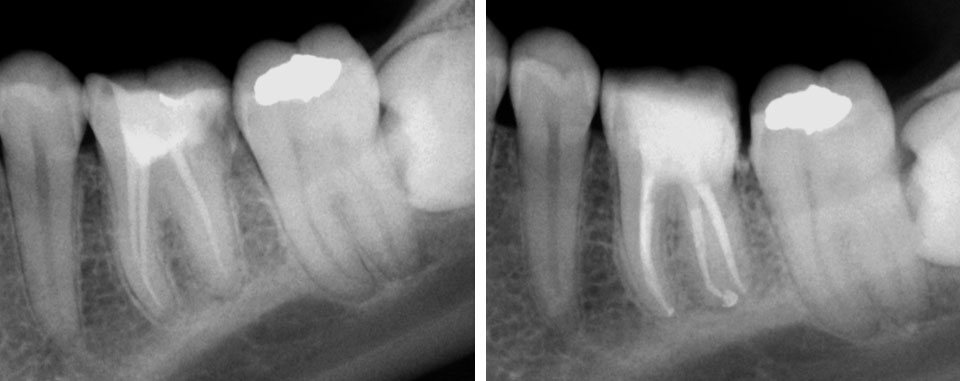

Age of patient: 15 years

Tooth: left mandibular first molar. Poor restorative prognosis. Very large lesion.

Work done: Obturation done after multiple calcium hydroxide dressings over 5 months and seeing lesion decrease in size. Fiber-post placed in distal canal. Core build-up done with Luxacore composite. Adv crown.

Notes: This is endo done for a “holding period” for implants later on. Healing of bone ensures a more favorable environment for implant placement.

Obturation done after 5 months of calcium hydroxide

May 2015 – 3 year recall

Pre-op & 3 year recall